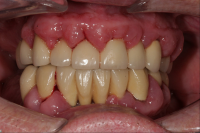

En volymökning av mjukvävnaden kring tänderna som är associerad med intag av läkemedel tillhörande grupperna antiepileptika, immunosuppressiva läkemedel och kalciumblockerare.

Inflammation är den utlösande faktorn som driver tillväxten av mjukvävnaden därför är plackkontroll av största vikt.

Förekomst av gingivala hyperplasier med djupa tandköttsfickor och svåra hygienförhållanden som följd.